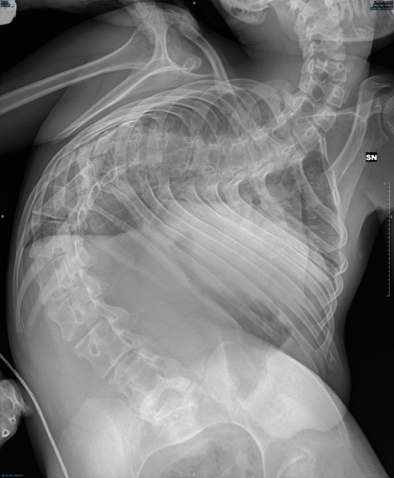

Questa particolare procedura, denominata “tecnica di correzione bipolare senza artrodesi”, è stata eseguita su due piccoli pazienti affetti da scoliosi molto grave. Inizialmente i genitori dei ragazzi si erano rivolti ad altre strutture sanitarie le quali però, data l’elevata complessità di entrambi i casi hanno deciso di non procedere chirurgicamente.

«La metodica utilizzata di “osteosintesi bipolare senza artrodesi” è una tecnica mini-invasiva epercutanea – commenta la dottoressa Monia Martiniani – che ha una grande rilevanza a livello internazionale e rappresenta oggi una valida alternativa in tutti i pazienti, in particolare quelli più gravi e fragili in cui le condizioni generali scadute renderebbero impossibile o particolarmente rischioso un intervento classico di correzione ed artrodesi vertebrale. Il trattamento inoltre prevede l’impiego di un sistema auto-allungante che, tramite un connettore a cremagliera, consente lo slittamento progressivo di due barre sfruttando la naturale crescita del bambino e le trazioni dovute ai movimenti spontanei e fisioterapia, eliminando la necessità di ricorrere a ripetuti interventi chirurgici di allungamento. Trattandosi di una procedura mininvasiva i tempi chirurgici sono di gran lunga inferiori rispetto ad un’artrodesi classica, con riduzione delle perdite ematiche, del rischio infettivo e dei tempi anestesiologici».

Spiega il professor Antonio Pompilio Gigante che «il trattamento delle gravi scoliosi, soprattutto neuromuscolari, ancora oggi è una grossa sfida anche per chirurghi vertebrali esperti, sia per la gravità della deformità vertebrale sia per le problematiche di carattere generale legate alle patologie di base che spesso affliggono questi bambini. Il trattamento non chirurgico in questi casi non è in grado di contrastare il peggioramento della scoliosi. Le moderne ed innovative tecniche chirurgiche introdotte negli ultimi anni presso i Presidi Salesi e Torrette dell’Azienda Ou delle Marche, anche grazie alla preziosa assistenza anestesiologica, hanno permesso il trattamento numerose deformità vertebrali molto gravi, in particolare pediatriche, spesso non trattate in altri centri. In particolare, il trattamento chirurgico precoce delle deformità vertebrali nelle malattie neuromuscolari ha dimostrato di aumentare la sopravvivenza di questi bambini riducendo il rischio di insufficienza respiratoria. Ad oggi questi sistemi sono una promettente opzione di trattamento presso la nostra Azienda».